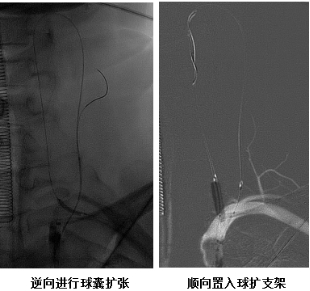

经过完善的术前准备,全麻状态下手术开始。李永利带领团队先用微导丝引领微导管进入颈升动脉,绕了几个圈后进入椎动脉内,然后在椎动脉内逆血流方向往回走,找到并通过闭塞段。使用球囊对闭塞段进行扩张,扩张后隐约可见血管再通的影像,再从闭塞近端正常血管内输送一枚支架将闭塞段血管完全支撑起来。手术非常顺利,术后检查显示,椎动脉供血明显充沛,患者次日头晕等症状明显好转。